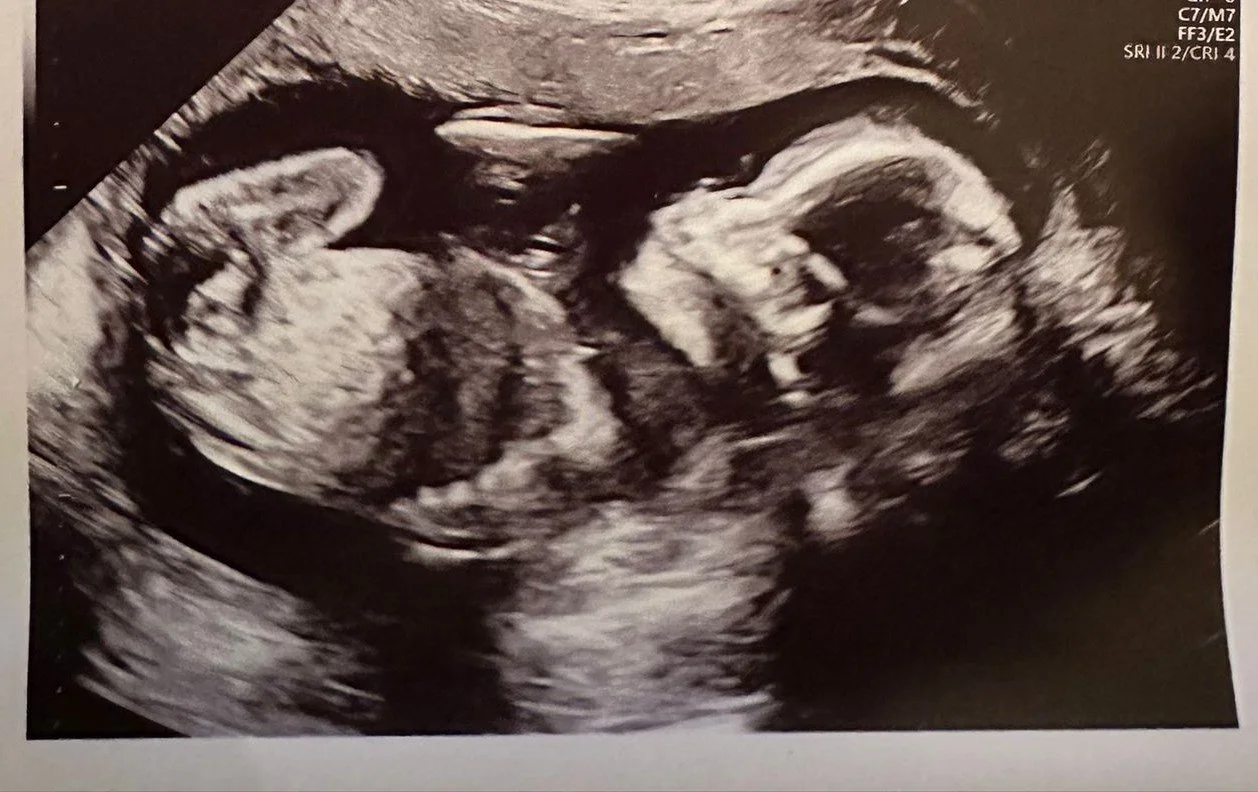

Is it a girl or a boy??

As many of you will already be aware James and his wife Anneli are expecting their 2nd child on 20th June 2025. In early February they had their 20 week scan & some of the team made guesses on what the sex of the baby would be with 4 voting girl and 6 voting boy.

James is now happy to annouce that all is progressing well and they are having another GIRL!!